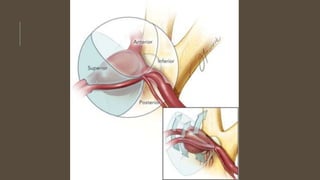

ANATOMY

• Anterior communicating artery communicate two anterior cerebral

arteries

• A1 segment of the Anterior cerebral artery runs from internal carotid

artery to anterior communicating arteries

• The junction of A1 and anterior communicating artery lies over optic

chiasm in 70% cases while over optic nerve in 30% of cases

• Rarely A1 segment is replaced by artery arising from carotid at level

of anterior clinoid and passes under ipsilateral optic nerve perceived

as misplaced A1 segment and this anomaly is strongly associated

with aneurysm

• Anterior communicating artery gives perforating branches to lamina

terminalis, anterior hypothalamus, septal nucleus, medial

paraolfactory nuclei, subcallosal cingulum and genu of corpus

callosum

• Two larger branches are subcallosal and medial callosal arteries